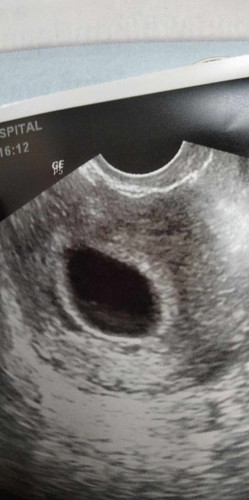

จะท้องลมไหม ประมาณ6-7วิก แต่หมอนัดอีก2อาทิตย์ค่ะ

8wก็ยังไม่เจอค่ะ หมอนัดอีก2อาทิตย์เพื่อคอนเฟิร์มว่ามีตัวอ่อนไหมค่ะ